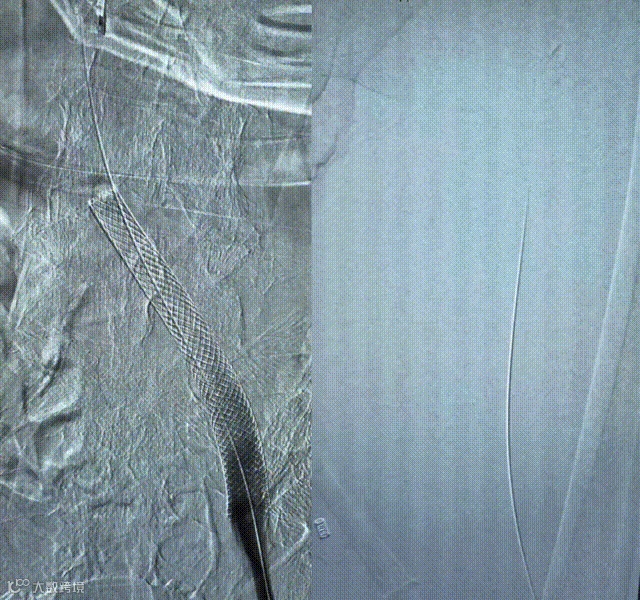

外周血栓抽吸导管:10F 45° 105cm,360°环向抽吸面积27.32mm

分离器:7mm 150cm分离器

10F弯头抽吸导管360°腔内旋转,tip头端保护血管内膜的同时,弯头设计利于清除附壁血栓

镍钛网篮血栓分离器对于质硬的附壁血栓,弧形杆设计能精准拴住大负荷血栓和陈旧性血栓,有利于血栓清除